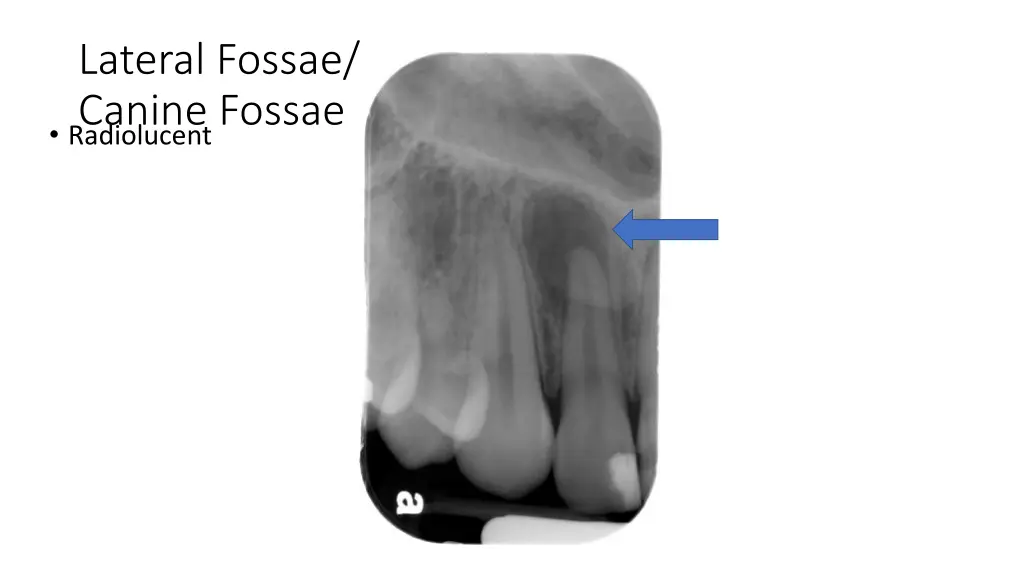

Lateral Fossae/ Canine Fossae Radiolucent